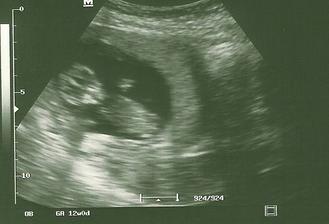

Naše druhé :o)

51 mm od hlavicky po zadok :o) a ty??